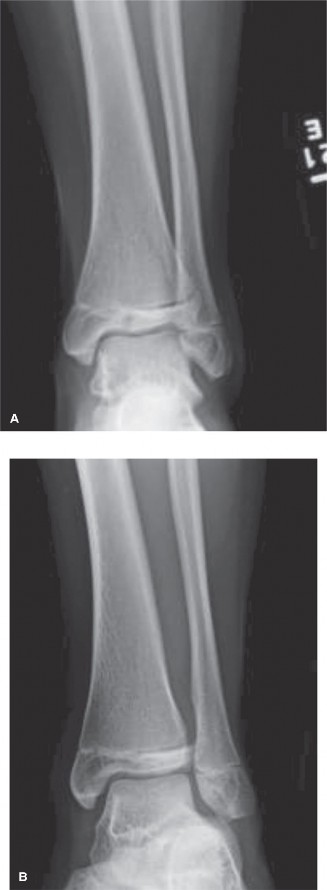

Potential for other intra-articular pathology with tibial tubercle fractures? CASE 10 You are called to the emergency room to evaluate a 13-year-old male complaining of acute right ankle pain. He reports that he injured his ankle earlier in the day when another player “took him out” during a soccer match. He was unable to bear weight through the right lower extremity and was brought promptly to the hospital for evaluation and management of his injury. An anteroposterior radiograph of the patient’s ankle is shown in Figure 10–14.

Figure 10–14

Which of the following answers correctly pairs the eponym commonly used to

describe this injury with the affected anatomic structure?

1. Tillaux fracture; ATFL (anterior talofibular ligament)

2. Tillaux fracture; AITFL (anterior inferior tibiofibular ligament)

3. Chopart fracture; ATFL (anterior talofibular ligament)

4. Chopart fracture; AITFL (anterior inferior tibiofibular ligament)

5. Chaput fracture; ATFL (anterior talofibular ligament)

Discussion

The correct answer is (B). The radiograph shown demonstrates a Tillaux fracture, the eponym used to describe transitional ankle fractures in adolescents characterized by two main fragments: one fragment being the anterolateral distal tibial epiphysis and the second including the tibial metadiaphysis, the physis, and the posteromedial epiphysis. On an anteroposterior radiograph, the fracture line appears to run through the physis and exit through the epiphysis. The anatomic structure attached to this piece is the anterior inferior tibiofibular ligament (AITFL), one of the primary syndesmotic ligaments of the ankle. Chopart injuries involve the midtarsal joint. The Chaput fragment is another eponym (used more commonly in adult ankle fractures) to describe the fracture piece that remains attached to the AITFL. The anterior talofibular ligament (ATFL) is the most commonly injured structure in lateral ankle sprains.

After reviewing the patient’s radiographic imaging, you diagnose an injury involving the growth plate of the distal tibia. Which of the following answers correctly pairs the description of this injury with its associated Salter–Harris fracture classification?

1. The fracture involves the physis only; Salter–Harris I or V

2. The fracture exits from the physis into the metaphysis; Salter–Harris III

3. The fracture exits from the physis into the metaphysis; Salter–Harris IV

4. The fracture exits from the physis into the epiphysis; Salter–Harris III

5. The fracture exits from the physis into the epiphysis; Salter–Harris IV

The correct answer is (D). The Salter–Harris classification system for describing fractures in skeletally immature individuals is as follows: Salter–Harris I fractures involve the growth plate only and are not usually evident on plain radiographs. This is usually a clinical diagnosis. Salter–Harris II injuries involve the physis (growth plate) and then the fracture line “exits” into the metaphysis (away from the joint).

This metaphyseal fragment is often called a “Thurston–Holland” fragment. Salter–Harris III injuries involve the physis and then the fracture exits into the epiphysis (towards the joint). The injury depicted in Figure 10–14 is a Salter–Harris III. Salter–Harris IV injuries involve the growth plate, with extension of the fracture into both the epiphysis and metaphysis. Salter–Harris V injuries are crush injuries through the growth plate that are often radiographically indistinguishable from Salter–Harris I injuries initially, but have higher rates of physeal arrest due to the increased force that produces this injury.